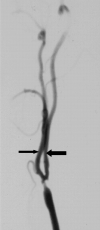

Background and purpose: Two large trials indicated that endarterectomy was less beneficial for symptomatic patients with internal carotid artery (ICA) near occlusion than for patients who had severe stenosis without near occlusion. Near occlusions complicate ratio calculations of ICA stenosis and require attention to detail for identification. The goal is to provide diagnostic criteria, illustrate identifying features, estimate accuracy of identification, and assess prognosis for patients with near occlusion.

Methods: We re-reviewed 1216 patients with severe (> or =70%) stenosis on angiography in the North American Symptomatic Carotid Endarterectomy Trial and European Carotid Surgery Trial. One of 5 (n = 262) had 2 or more criteria for near occlusion: (1) delayed cranial arrival of ICA contrast compared with external carotid artery (ECA); (2) intracranial collaterals seen as cross-filling of contralateral vessels or ipsilateral contrast dilution; (3) obvious diameter reduction of ICA compared with opposite ICA; or (4) ICA diameter reduction compared with ipsilateral ECA.